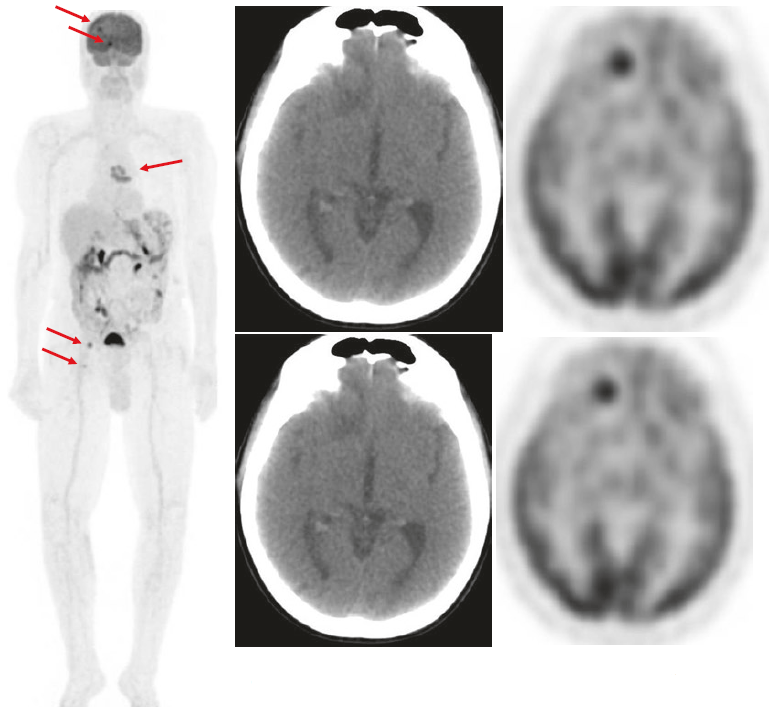

Ristadiazione di melanoma avanzato dopo trattamento locale.

Di solito, la scansione PET-FDG ha un valore limitato per la rilevazione delle lesioni secondarie cerebrali; tuttavia, l’elevato assorbimento delle lesioni da melanoma consente di rilevare anche le metastasi cerebrali. Va sottolineato che la risonanza magnetica (RM) rimane il metodo elettivo per la valutazione delle lesioni cerebrali.